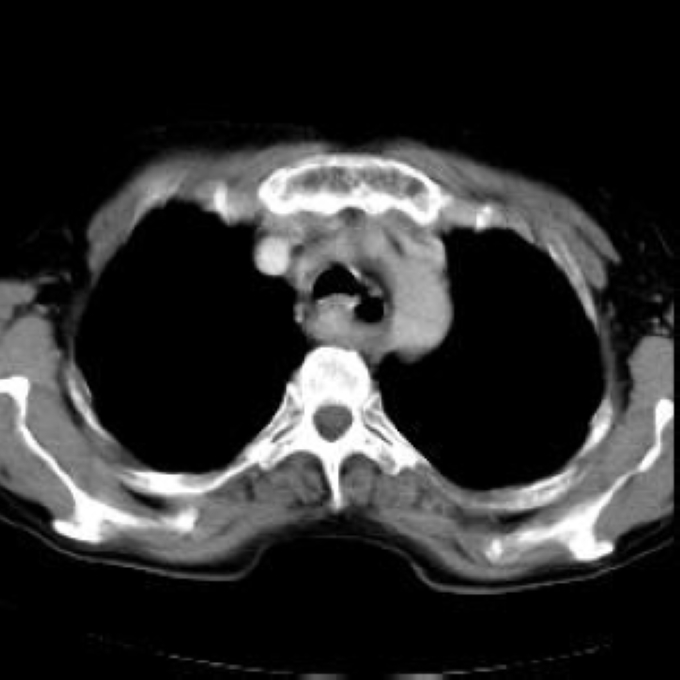

Arteria lusoria.

56 year old patient with dyspagia. A tumor of soft tissue was described in upper mediastinum on plain X-ray of the thorax. What is this mass in the upper mediastinum?